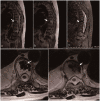

This case report describes a rare giant bone island combined with hemangioma diagnosed in a patient with osteolytic vertebral metastases. The bone island's greatest diameter was 3.15 cm, and bone islands of this size are rare in the literature. This article aims to provide clinicians with information about the diagnosis and relevant literature of bone islands.